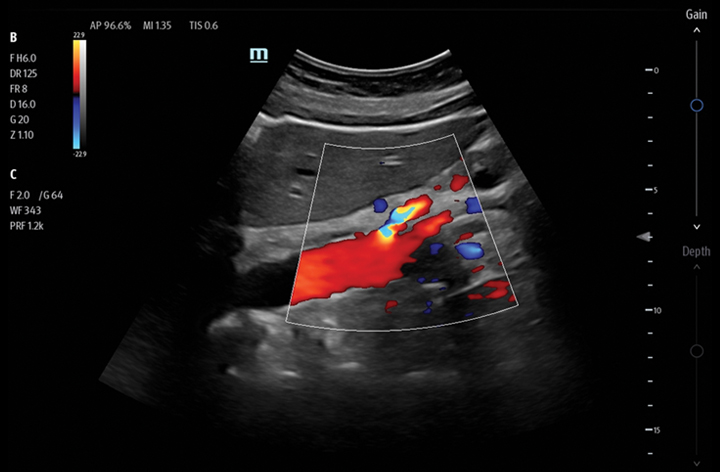

The TE7 Max Ultrasound System is designed to maximize your capabilities in demanding Point of Care environments. With its thoughtful industrial design and best-in-class image quality, the

TE7 Max provides a superior user experience during rapid clinical assessments and procedures taking place at the patient’s bedside

or on the go.

The TE7 Max boasts a large 21.5” vertically oriented high-definition display and a sealed touch-based interface to optimize visualization and accessibility when every second counts. The TE7 Max also incorporates a comprehensive suite of artificial intelligence (AI) powered Smart Tools and workflow enhancement software (iWorks™ Protocol) making efficiency and reproducibility the expectation for all end users.